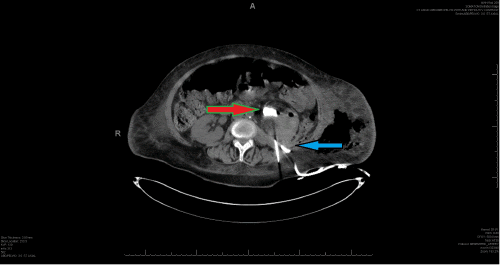

D) Status postpercutaneous left nephrostomy (red arrow) and catheter drainage of the left retroperitoneal abscess (blue arrow)

The patient's white blood cell (WBC) count was 16,000/uL; she was admitted to the intensive care unit and started on cefepime, followed by the percutaneous insertion of a left nephrostomy tube for decompression of her hydronephrosis on hospital day 2, which drained 3L of purulent fluid. On the same day (HD2), she underwent percutaneous drainage of her left-sided retroperitoneal abscess, yielding 300ml of purulent fluid. Fluid cultures from the abscess drainage revealed Streptococcus anginosus and Proteus mirabilis. Blood cultures were negative, and multiple tests for COVID-19 were negative. The patient continued to recover slowly.

On hospital day 9, the patient's nephrostomy tube was accidentally dislodged. The patient underwent a repeat CT scan for its replacement, as her sepsis was still resolving, and it was deemed to still be necessary. This study showed a pyelocolonic fistula, a persistent, large, left staghorn renal calculus, and an apparent fungal ball in the left kidney (Figure 2). Cultures from her urine grew Candida albicans and Escherichia coli, which were treated with meropenem and fluconazole.